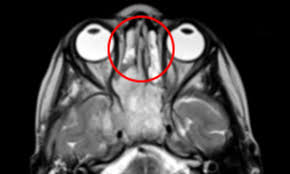

During a nasal endoscopy, a thin tube with a light and camera on the end is inserted into your nose. Nasal cavity cancers are usually removed by a wide local excision. Sinus and nasal cavity cancer can form as a tumor (or tumors) in two places: In fact, many of these symptoms are more likely to be caused by other conditions. The technical terminology for nose cancer, nasal adenocarcinoma is a type of tumor found in a dog's nasal cavity and paranasal sinuses. Picture nasal cavity and paranasal sinus cancer: Nasal cancer in cats my cat was rubbing his face on the ground constantly. this is a real statement from one owner of our pet hero pet that received treatment for nose cancer. Being exposed to certain chemicals or dust in the workplace can increase the risk of paranasal sinus and nasal cavity cancer.

The camera sends pictures to a monitor that your doctor uses to look for anything unusual. Nasal tumors are found in the nasal cavity and the paranasal sinuses and affect cats. Men are more likely to get sinus cancer than women. Which type of tumor you have helps determine the best treatment for you. Medical illustrations in pictures of sinus cancer article related to pictures of sinus cancer :

Nose and sinus cancer is a condition in which abnormal cell growth occurs in the nasal cavity, sinus passages, or surrounding tissues. The nasal cavity is the passageway just behind your nose. Air passes through it on the way to your throat as you breathe. Tests and procedures used to diagnose nasal and paranasal tumors include: They are locally invasive and do not normally spread but are almost always malignant. Men are more likely to get sinus cancer than women. Nasal and sinus cancer is different from cancer of the area where the nose and throat connect. It explains the factors that may increase the chance of developing nasal cavity or paranasal sinus cancer and what people can do to lower their risk.use the menu to choose a different section to read in this guide. Still, if you have any of these symptoms, it's important to have them checked by a doctor so that the cause can be found and treated, if needed. Symptoms of nasal cancer in dogs In fact, many of these symptoms are more likely to be caused by other conditions. The nasal canal expands, so you can examine the nasal cavity in detail. Modern equipment makes it possible to study the nasal cavity without injury by displaying an image on a monitor and at the same time taking tissue samples for additional research.